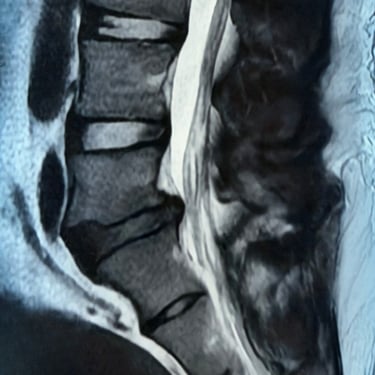

Listesis Lumbar L5–S1 por Fractura Ístmica: Estabilización con FTP y TLIF

La listesis lumbar L5–S1 por fractura ístmica se produce por un defecto en la pars interarticularis que genera inestabilidad vertebral, dolor lumbar crónico y compromiso radicular. Cuando el tratamiento conservador no es efectivo, la artrodesis lumbar con fijación transpedicular (FTP) asociada a la fusión intersomática transforaminal (TLIF) es una alternativa quirúrgica eficaz. Este procedimiento permite descomprimir las raíces nerviosas, restaurar la alineación vertebral y lograr una fijación sólida del segmento afectado. La combinación de estabilización y fusión reduce el dolor, mejora la función y favorece una recuperación segura y progresiva.